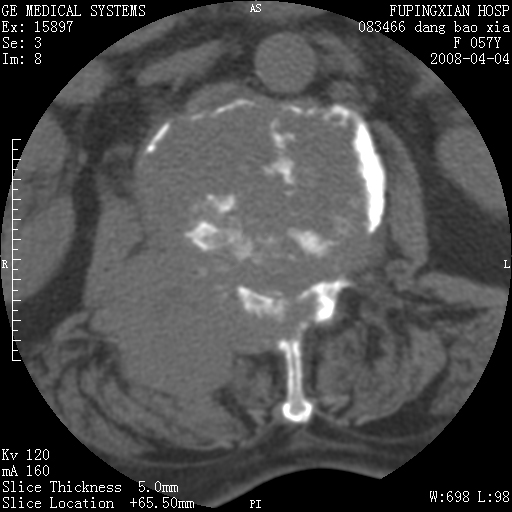

标题: CT12677:女性,57岁,疼痛数月。 [打印本页]

标题: CT12677:女性,57岁,疼痛数月。

椎体及附件骨质破坏同时伴软组织肿块,首先考虑恶性肿瘤。

椎体及附件骨质破坏,伴软组织肿块,首先考虑恶性骨肿瘤,建议提供正侧位片。

骨组织起源,膨胀,软组织肿块=恶性改变:首选骨巨,其次转移瘤,再次脊索瘤

椎体及附件溶骨性破坏,周围巨大软组织肿块,首先考虑转移瘤。